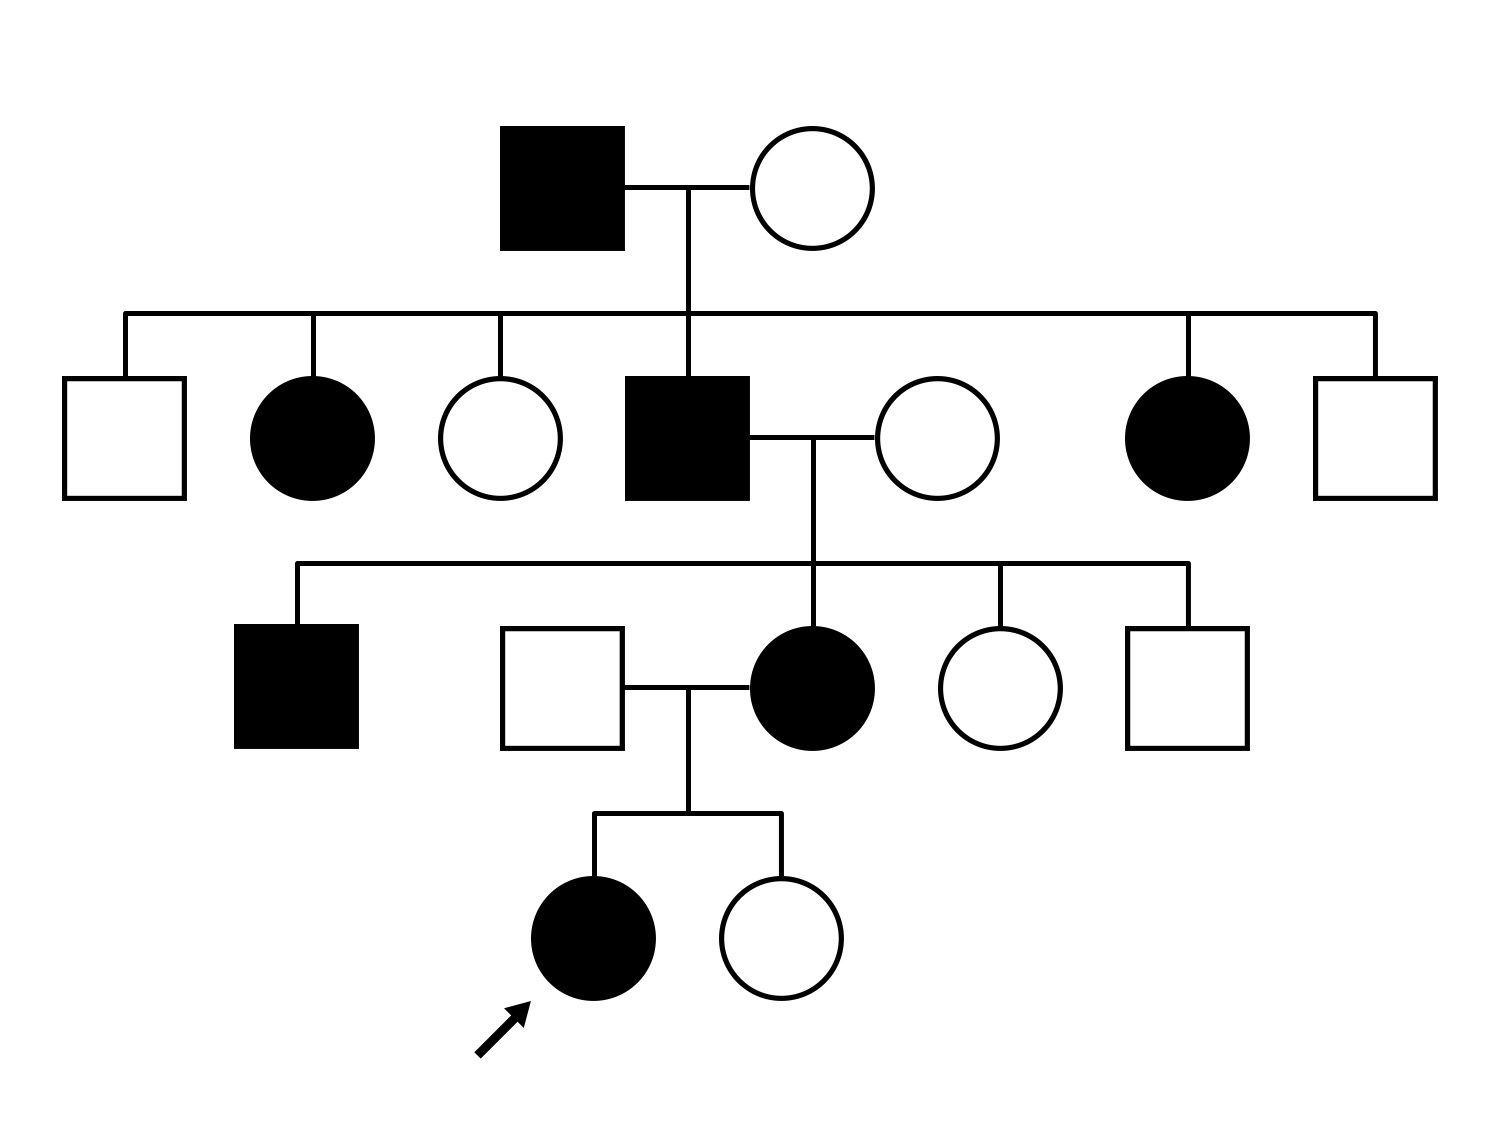

This 59 year old woman first noticed a reduction in her visual acuity and photophobia in her late teens.

| Disease | Gene | Allele 1 variant(s) | Allele 2 variant(s) | Inheritance mode |

|---|---|---|---|---|

| AD Cone and Cone Rod Dystrophy | GUCA1A | Glu155Gly GAG>GGG | AD |

Glu155Gly GAG>GGG

AD